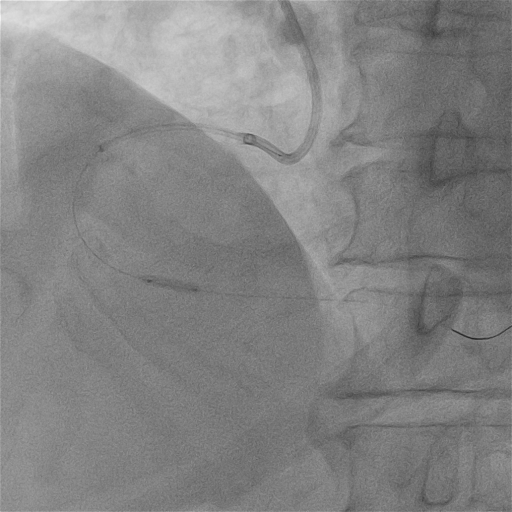

我院右冠基础造影

RCA:全程弥漫多处95%以上狭窄伴重度钙化,最重处次全闭塞,血流TIMI2级。